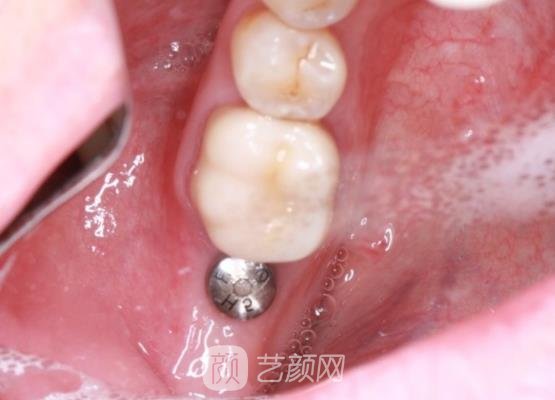

接下来手术就开始了,手术过程中我没有感觉到什么剧烈的疼痛感,可能是因为采用了麻醉剂的原因,只能感觉到牙龈处的肌肉一直在动,短短几个小时手术就结束了,没有浪费我很多的时间。

刚结束手术时,我的牙龈处有一些肿胀的情况,还很疼,医生告诉我这些情况比较正常,让我不用太过于的担心,然后按照我的肿胀情况给我开了几副消炎药,让我定时服用,吃了消炎药以后,果然我的牙齿的情况好了很多,也不怎么疼了。

几个月以后,我一直按照医生的话,谨慎的对待我的术后护理注意事项,果然现在我的种植牙已经恢复的很自然了,而且口腔里面也没有什么异物的感觉,基本上找不到手术的痕迹,真的就像是我自己的牙齿一样,果然手术还是有成果的,对于手术我真的很满意。